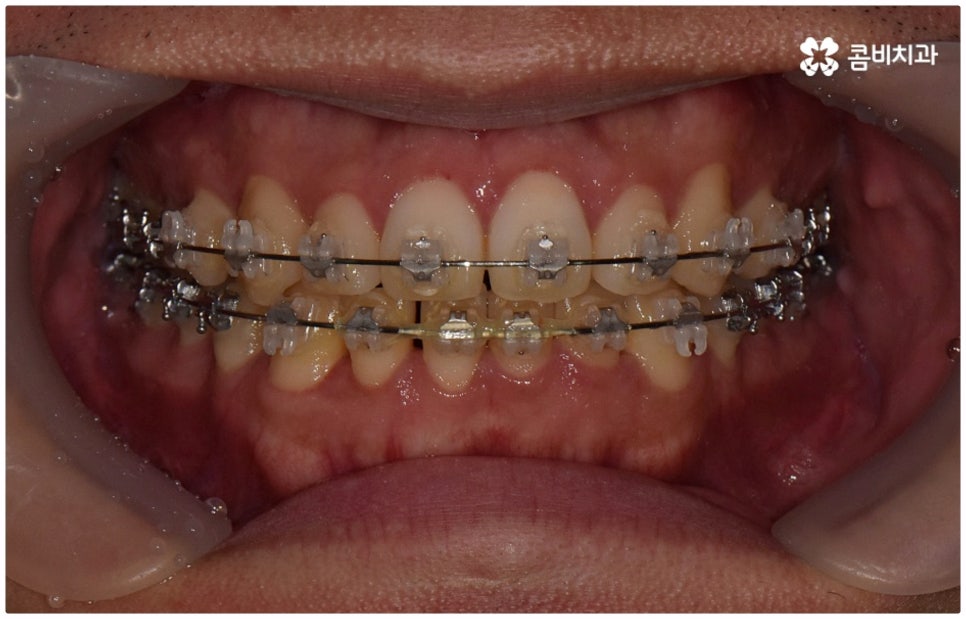

물론 교정 치료에 적기가 정해져 있는 것은 아니기 때문에 성인 이후 중장년 환자분들이라도 교정 치료가 불가능하지는 않으며 상황에 따라 비수술적인 방법으로도 얼마든지 불편함을 줄일 수 있는 경우가 있으니 정확하게 진단한 후 각자에게 맞는 교정 계획을 세워 무리하지 않게 치료를 진행하시길 바라고 있어요. 특히 턱관절과 관련된 부분을 개선하기 위해서는 양악 수술 밖에 방법이 없는 것이 아닌가 생각하셨던 분들이라면 먼저 치과에 내원하셔서 검진과 상담부터 진행해 보시면 마음의 부담을 덜 수 있어 좋을 거예요. 부정교합 3급 치열 (절단교합과 일부 반대교합이 병행되어 있음) 을 가지고 있는 성인분도 교정 치료를 통해 훨씬 자연스럽게 개선이 가능할 수 있으며, 관련 기술 개발 및 미니스크류 등 여러 장치의 발전을 통해 예전에는 적용이 어려웠던 케이스들도 이제는 교정 치료의 도움을 받을 수 있습니다.

위 사진은 이해를 돕기 위한 이미지이며, 환자의 동의하에 진행되었습니다.

전체 치료 기간은 약 18개월이 소요되었으며,

개인에 따라 출혈 및 부작용이 발생할 수 있고,

환자마다 치료 결과 및 기간이 상이할 수 있으므로,

정확한 치료 기간 및 치료 계획은

치과에서 상담을 받아보시길 권장 드립니다.